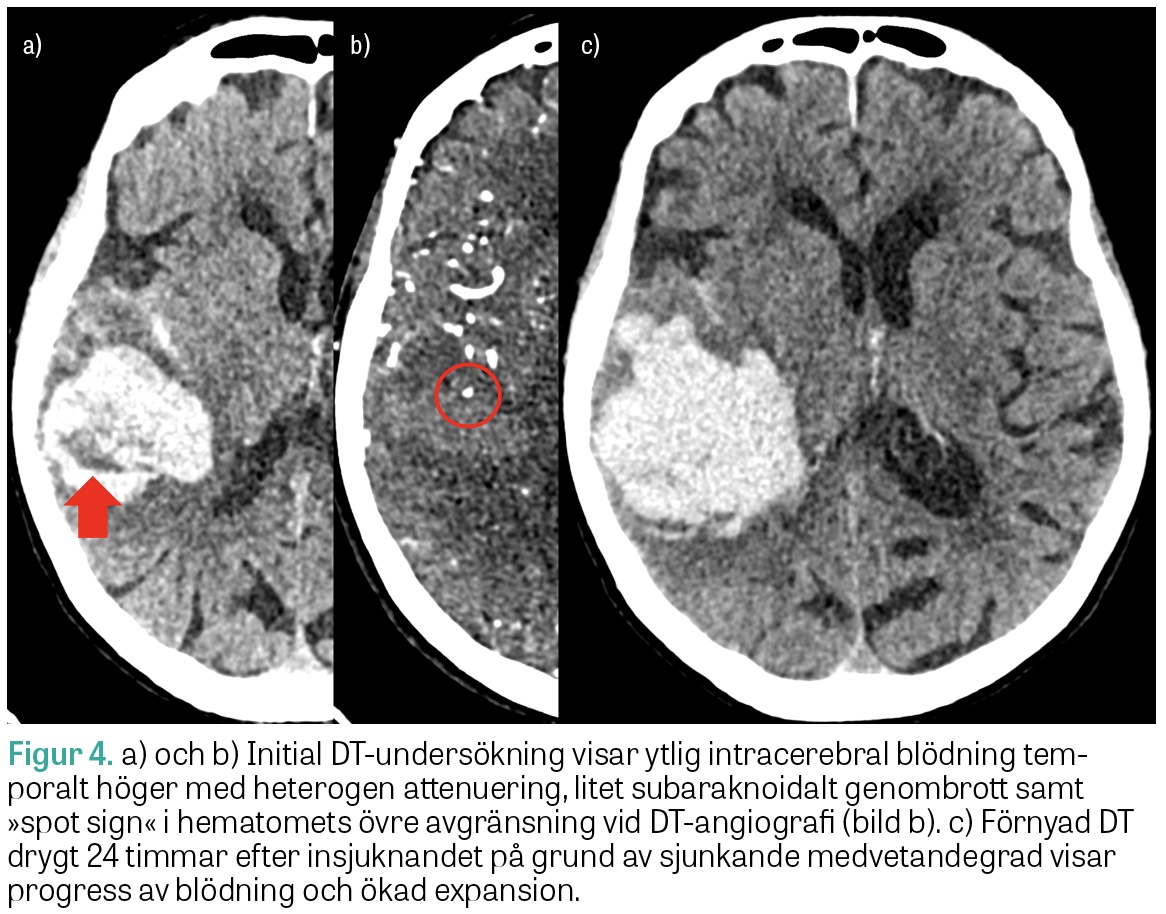

ICH med heterogen attenuering och oregelbundna marginaler på DT har ökad risk för expansion under det första dygnet (Figur 3). Även så kallat »spot sign« på DT-angiografi, det vill säga kontrastmedelsutträde i hematomet, har hög specificitet för blödningsexpansion men låg sensitivitet och utesluter inte risken för expansion. Fynd på DT eller DT-angiografi förknippade med hög risk för fortsatt hematomexpansion kan bidra vid bedömning av lämplig vårdnivå och vid ställningstagande till överföring till universitetssjukhus för övervakning inför even­tuell neurokirurgi.

Ny DT utan kontrast bör utföras akut vid klinisk försämring, och en uppföljande DT-kontroll är generellt motiverad 12–24 timmar efter den initiala undersökningen för att se om hematomet har expanderat och om det finns begynnande hydrocefalus, då båda dessa påverkar fortsatt prognos.

Figur 4.